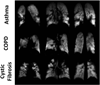

By permitting direct visualization of the airspaces of the lung, magnetic resonance imaging (MRI) using hyperpolarized gases provides unique strategies for evaluating pulmonary structure and function. Although the vast majority of research in humans has been performed using hyperpolarized (3)He, recent contraction in the supply of (3)He and consequent increases in price have turned attention to the alternative agent, hyperpolarized (129) Xe. Compared to (3)He, (129)Xe yields reduced signal due to its smaller magnetic moment. Nonetheless, taking advantage of advances in gas-polarization technology, recent studies in humans using techniques for measuring ventilation, diffusion, and partial pressure of oxygen have demonstrated results for hyperpolarized (129)Xe comparable to those previously demonstrated using hyperpolarized (3)He. In addition, xenon has the advantage of readily dissolving in lung tissue and blood following inhalation, which makes hyperpolarized (129)Xe particularly attractive for exploring certain characteristics of lung function, such as gas exchange and uptake, which cannot be accessed using (3)He. Preliminary results from methods for imaging (129) Xe dissolved in the human lung suggest that these approaches will provide new opportunities for quantifying relationships among gas delivery, exchange, and transport, and thus show substantial potential to broaden our understanding of lung disease. Finally, recent changes in the commercial landscape of the hyperpolarized-gas field now make it possible for this innovative technology to move beyond the research laboratory.